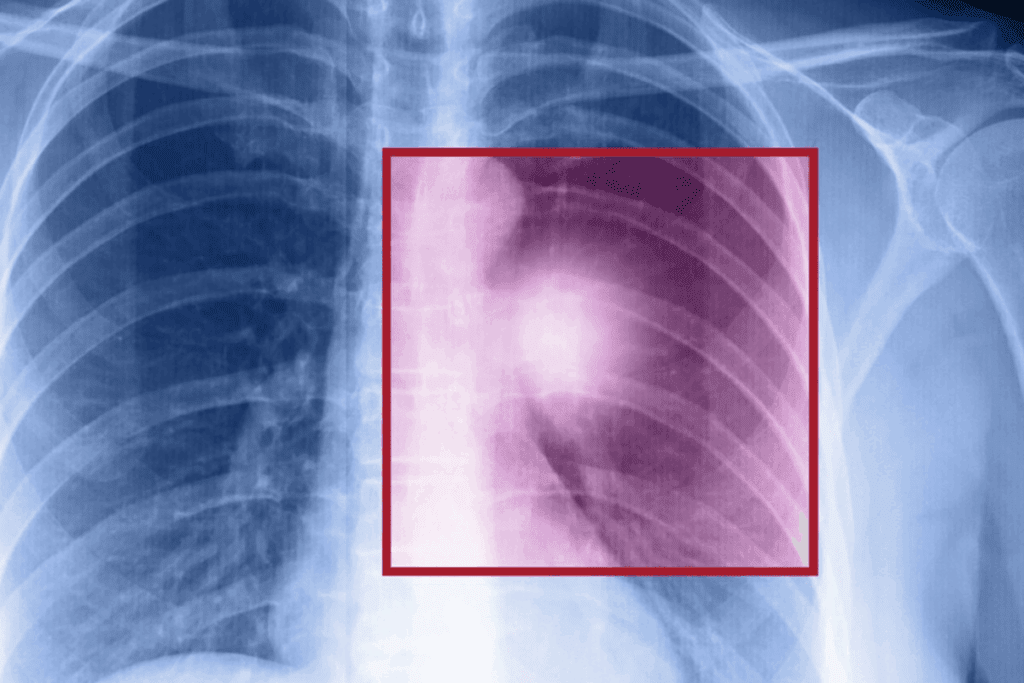

Regular check-ups with healthcare providers are important to track rib healing. We use X-rays to check the healing and adjust the plan as needed.